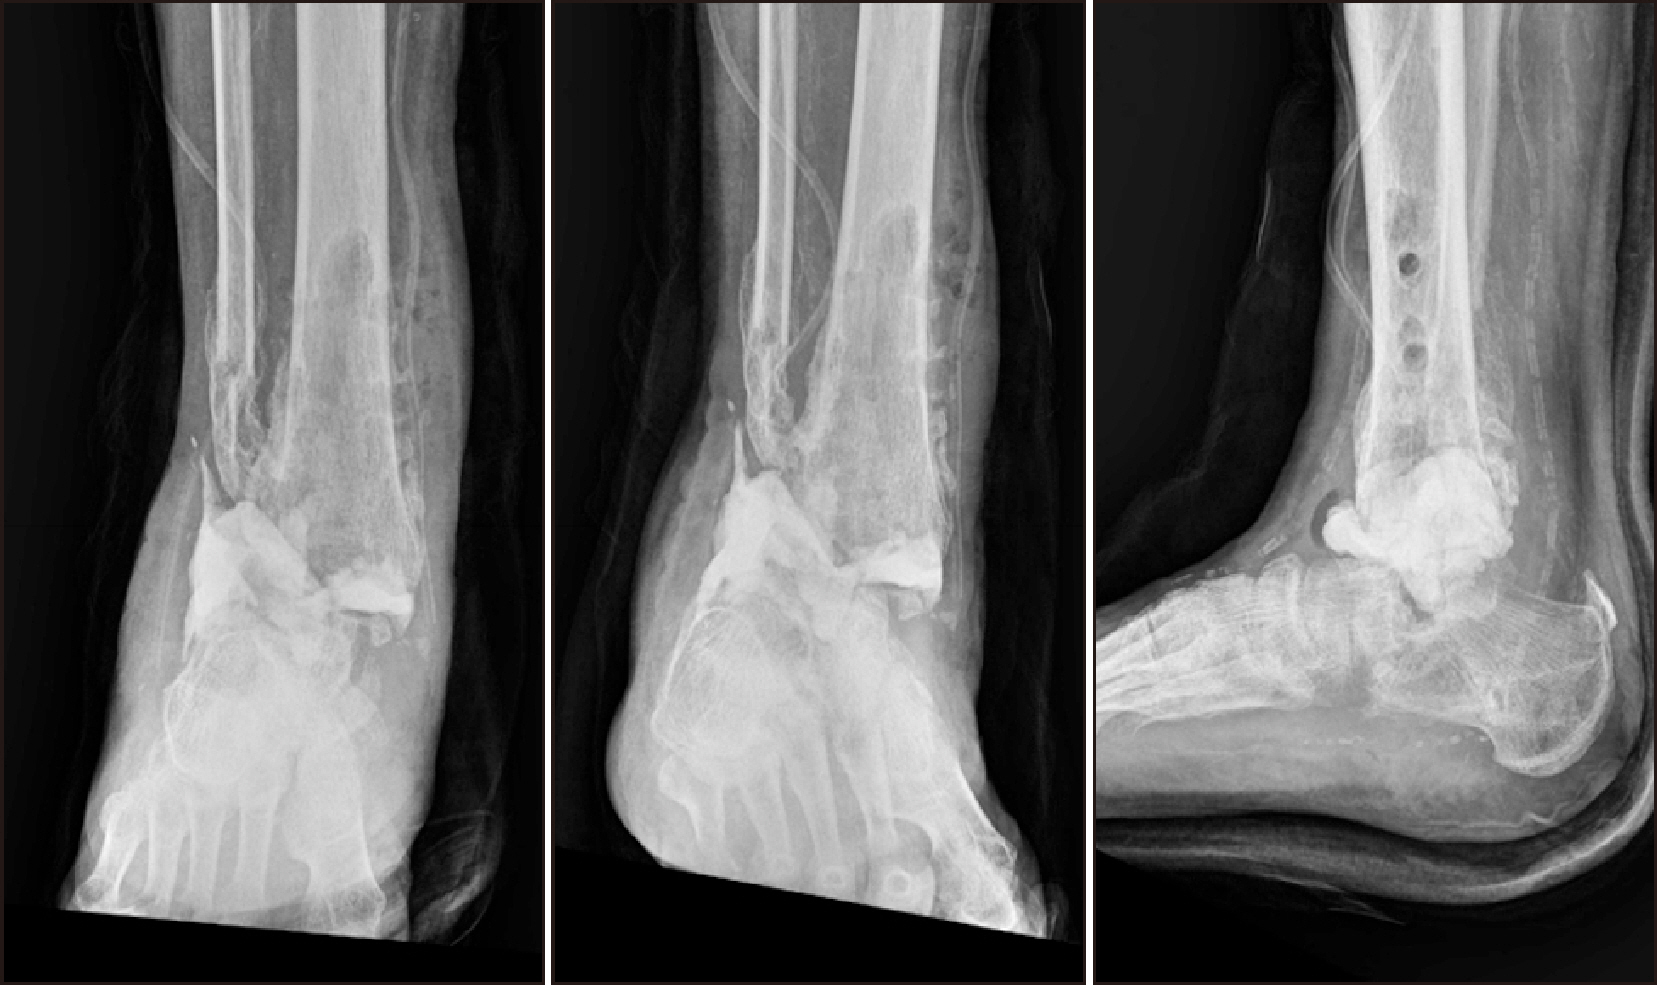

Comprehensive Management of Presumed Underlying Charcot Arthropathy with a Subsequent Traumatic Ankle Fracture in a Patient with Diabetes Mellitus, End-Stage Renal Disease: A Case Report

Charcot neuroarthropathy (CN), also known as Charcot arthropathy, is a complex, progressive disorder primarily affecting the foot and ankle. This case report describes a multifaceted management strategy for a 54-year-old male with diabetes mellitus, end-stage renal disease, and presumed underlying Charcot arthropathy who experienced a traumatic ankle fracture. The initial surgical plans were delayed because of systemic infection indicators, including elevated C-reactive protein levels and high fever. The patient underwent multiple surgical interventions and faced challenges, including metal failure, implant-associated infection, and tibiotalar joint dislocation. A multidisciplinary approach involving orthopedic surgeons, nephrologists, and endocrinologists was crucial for managing the case effectively. In particular, the patient declined a below-knee amputation and opted for comprehensive surgical intervention, resulting in improved functionality at the latest follow-up. This case highlights the complexities of managing CN in patients with multiple comorbidities and emphasizes the need for a nuanced, patient-centered approach.